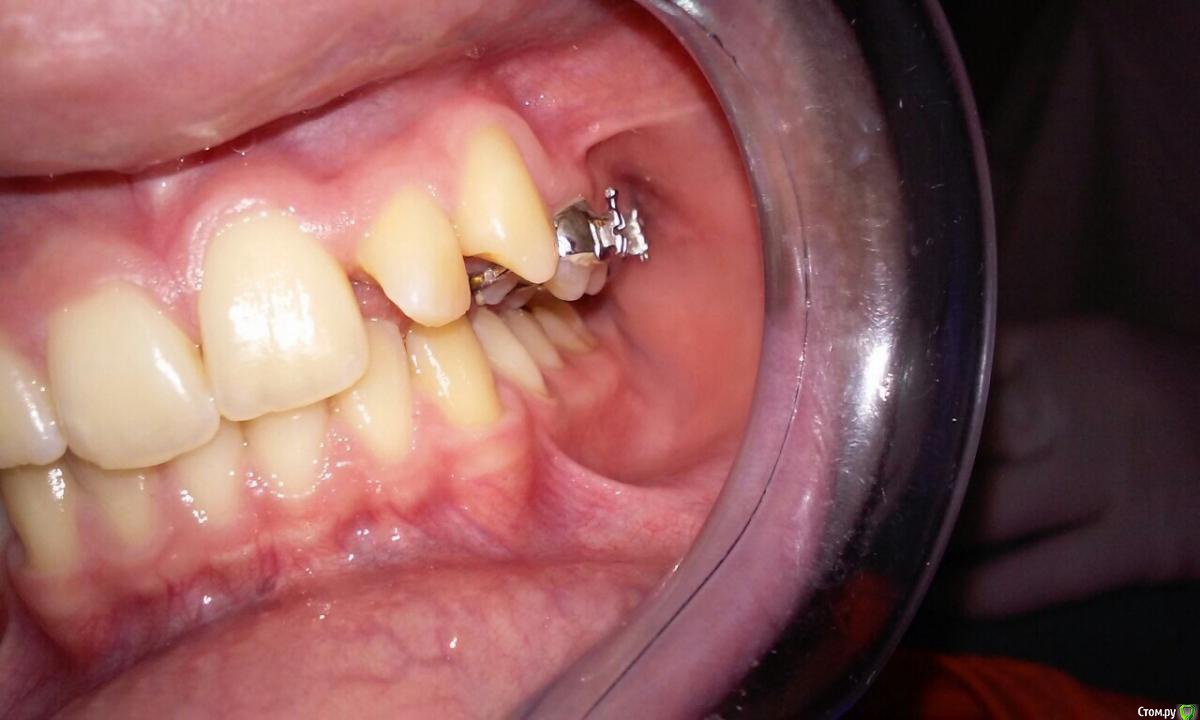

natkoorth1991 Опубликовано 28 августа, 2015 Поделиться Опубликовано 28 августа, 2015 мальчик, 13 лет, премоляры удалять не хотели, поставила хайракс на в / ч- получила перекрестную окклюзию. Извините за плохие фото( Что теперь делать? фото после: Ссылка на комментарий

natkoorth1991 Опубликовано 29 августа, 2015 Автор Поделиться Опубликовано 29 августа, 2015 там 22 повернут был , плюс клыки выпирали, считала , считала - больше 8 мм получилось.. побоялась, что протрузия сильная будет, плюс там явно сужение в обл премоляров( получается сейчас хайракс просто снять и поставить начальную нитиноловую или есть смысл брекеты плюс хайракс как ретенция, а когда клыки и двойка станут снять аппарат. Брекеты на низ сразу или позже лучше ставить?) Ссылка на комментарий

Yana guapa Опубликовано 29 августа, 2015 Поделиться Опубликовано 29 августа, 2015 конечно, показаний для PRE здесь не было. но раз уж поставили, то поставили.Я бы теперь скручила винт в обратную сторону. будет нужный результат. Потом сняла бы аппарат и просто сделала бы перерыв. Премоляры сами немного вернуться к исходному положению Нет ТРГ. Но стакой инклинацией верхних центральных резцов могу предположить, что НЧ смещена кзади. Если это выяснится, и в ходе лечения НЧ будем перемещать вперед, то это тоже поспособствует лучшему смыканию. ждем снимков 2 1 Ссылка на комментарий

Maverick Опубликовано 29 августа, 2015 Поделиться Опубликовано 29 августа, 2015 Хайрекс был не по показаниям. Обычная брекет система с этим справилась бы прекрасно. Снимайте его. Пока костная мазоль не образовалась переживать не надо, а это обычно занимает 4-5 месяцев, сняв аппарат получите рецидив и все вернется на круги своя. Либо как предложили выше скручивайте назад такими же темпами. Брекеты не ставьте пока не получить изначальную форму дуги, ну или близкую к ней. Трг это конечно хорошо, но надо смотреть на профиль - это показатель лечения, слепо доверять цифрам не совсем хорошая идея. Лечим не цифры, а людей. 2 1 Ссылка на комментарий